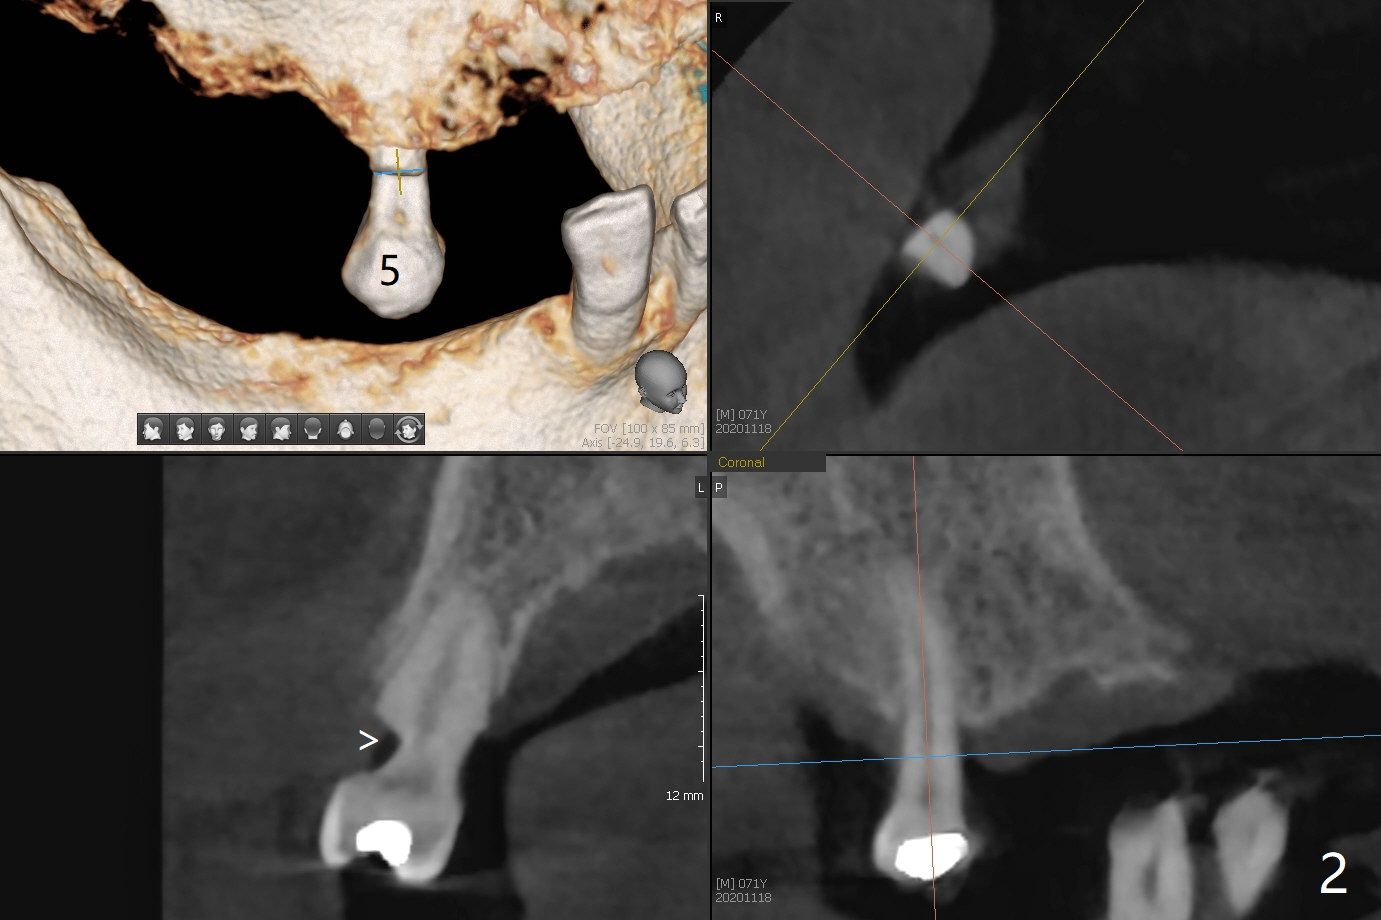

71岁男主诉下颌局部托牙松动(图一),侧切牙不适,临床检查显示后者有咬合创伤,局部卫生不佳,对策:洗牙以及左下4,6植入植体,放置带有球的基台(图五,六)。上颌局部托牙有三个自然牙,挺稳定,但是颈部缺损严重,需要修补(图二,三),左上5远中龋齿需要根管治疗(图四),尽量延长基牙寿命。一个月后病人回来却要求处理松动疼痛右下2,不愿意种植,与3固定和调整咬合,症状消失。Return to No Caries Overdentures Xin Wei, DDS, PhD, MS 1st edition 11/18/2020, last revision 12/13/2020